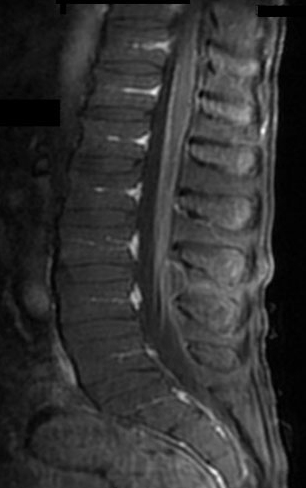

The magnetic resonance imaging technique is accompanied to diagnose this syndrome. The MRI of this syndrome shows lesions of the spinal cord as discontinuous and multiple. The cord lesions are also not necessarily present in the most caudal region of the conus. The nerve root enhancement is usually typical and may be either diffused or confined to the ventral or dorsal roots.